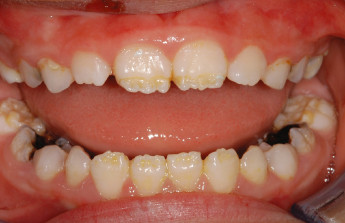

Enamel is the hard, protective outer layer of your teeth. Enamel hypoplasia is a defect of the enamel that only occurs while teeth are still developing. Still, it can affect both baby teeth and permanent teeth. The condition results in thin enamel, which makes your teeth vulnerable to dental decay.

The visual signs of enamel hypoplasia include white spots, pits, and grooves on the outer surface of the teeth.

Some of the signs of enamel hypoplasia are obvious, but others are more difficult to detect and may not be noticeable until they cause major dental problems. Having thin tooth enamel can lead to:

pits, tiny groves, depressions, and fissures

white spots

yellowish-brown stains (where the underlying layer of dentin is exposed)